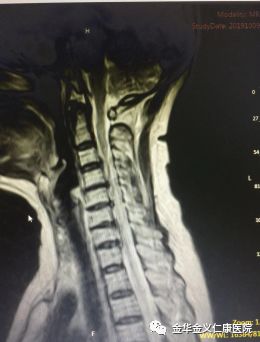

朱大妈入院后,医院给她做了全面的检查,诊断为神经根型颈椎病,增生的骨赘和突出的椎间盘,把第6、7两节神经根紧紧地压住了。考虑到病人惧怕手术,医院给予了积极的保守治疗。挂瓶、吃药、理疗………,但是疼痛仍然没有缓解,最后连下地都会导致肩臂部无法忍受的疼痛。徐煜院长根据病人的症状及磁共振的检查情况,估计神经根的压迫不解除,疼痛就无法缓解,但是病人对手术非常恐惧及抵触。经过与病人及家属的积极沟通,最终病人同意手术。

10月15日下午,经过两天的积极准备,由徐煜院长亲自操刀,为病人做了增生骨赘及突出椎间盘的切除手术。手术做得非常顺利。术后当晚,前几天痛得要死要活的她,疼痛完全消失,美美地睡了一觉。术后在全科医护人员的悉心照护下,身体状况恢复很快,术后第三天,就在家人及护理人员的协助下下地行走了。术后患者感慨地说,知道手术效果这么好,恢复这么快,我早就应该考虑手术了,起码可以少吃很多苦头!

术前术后对比